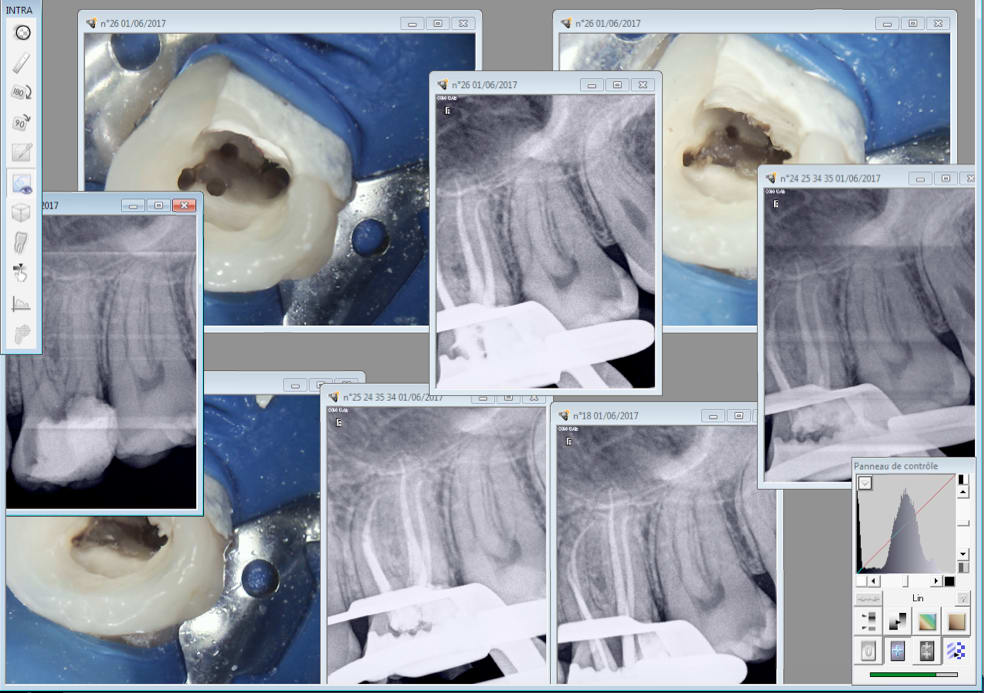

Localisateur dentjoy mini et CA chinetoc . Bon j'ai fini au R25 mais je pense que j'aurais pu finir au protaper gold.

( séquence SX et S1 gold puis R 25)

T'emmerdes pas à dépenser une fortune.

01/06/2017 à 13h06

On gagne à tous les coups. Et en 45 mn max. -)